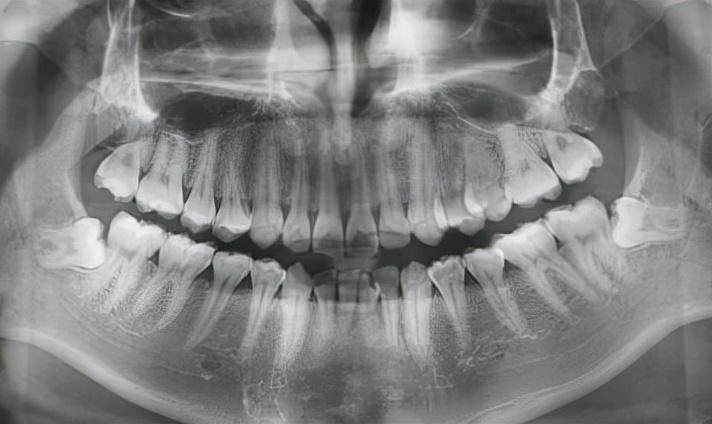

② 拔除完全長出的下頜智齒,難度系數(shù):★★

下頜智齒根據(jù)個人不同情況,拔牙的難度也各不相同。

垂直長出的比較好拔,跟上頜智齒拔牙操作起來差不多。這兩種拔牙手術(shù)的難度都不太大,

因此手術(shù)價格也不高,術(shù)后愈合也快。

下頜智齒垂直生長